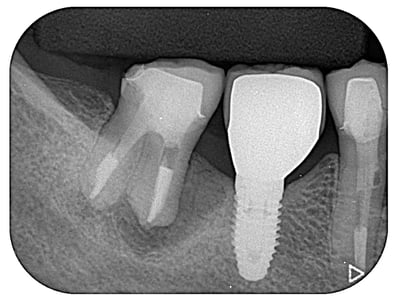

”穿孔”とは、簡単に言えば、歯の中に異常な”穴”が開いていることです。通常なら明らかに抜歯と診断されても不思議ではない症例ですが、時間をかけて修復しました。奥は他院で行ったインプラントですが、問題なく機能しています。

治療期間:約6ケ月

治療回数:11回(1~2回/月)

治療費:30万円(穿孔修復+根管治療+支台築造+セラミックス・クラウン)※毎回の処置料は別途

リスク:再治療は困難なこと。

※リスクはどのような治療にも必ずあること。

(そもそも抜歯の症例)

※この症例はのちに、根管外から穿孔部を再封鎖しました。

治療後2.5年経過しました。(2022年4月04日時点)

力及ばず、残念ながら、2023(R5)年4月 抜歯になりました。